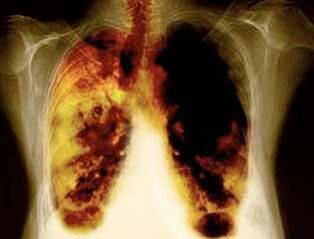

- Smanjenje rizika od razvoja raka pluća i mnogih drugih vrsta raka.

- Smanjenje rizika od razvoja određenih bolesti pluća (na primjer, kronična opstruktivna bolest pluća).

- U razdoblju od 2 tjedna do 3 mjeseca nakon odbacivanja pušenja, rad pluća se poboljšava i osjeća se nalet snage.

- Nakon 1-9 mjeseci, odvija se kašalj i kratkoća daha: cilija (sitne dlake) počinju normalno liječiti sluz, čisti pluća i smanjujući rizik od infekcije.

- 10 godina nakon prestanka pušenja za 40%, vjerojatnost raka pluća smanjuje se za 40%.